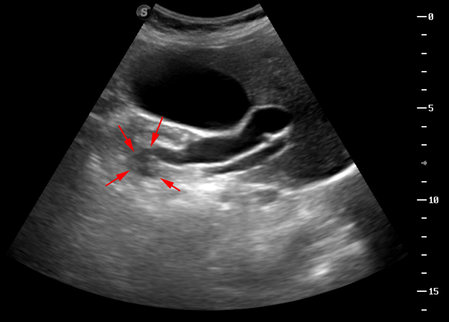

Опухоль головки панкреас - работа над ошибками

Пожилая женщина, без особых жалоб.

Сразу скажу, что опухоль я позорно просмотрел, хотя выявил признаки билиарной гипертензии.

Пересмотрите еще раз второй клип - вот как могут выглядеть признаки начальной панкреатической гипертензии.